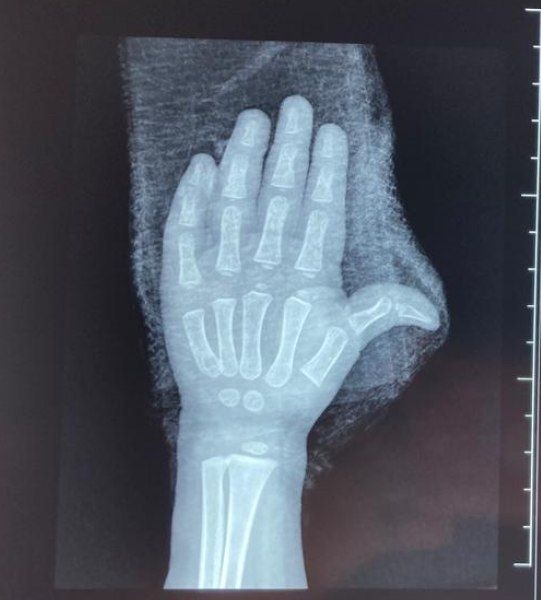

Los servicios de auxilio tardaron aproximadamente 20 minutos en llegar para liberar los dedos de la menor. Hasta el momento, se desconoce la identidad de la niña y su madre, así como el estado actual de la mano de la pequeña.

La niña afortunadamente no perderá ningún dedo tras el accidente

La actualización sobre el estado de la niña indica que la sometieron a una intervención quirúrgica, en la cual los cirujanos plásticos lograron preservar sus dedos, lo que reduce cualquier riesgo de secuelas a largo plazo.

Imagen

Se informó que a la niña la dieron de alta de alta y ya se encuentra en proceso de recuperación y rehabilitación. Las autoridades locales instan a la vigilancia y precaución de los padres o tutores al utilizar instalaciones como escaleras eléctricas para prevenir este tipo de incidentes.